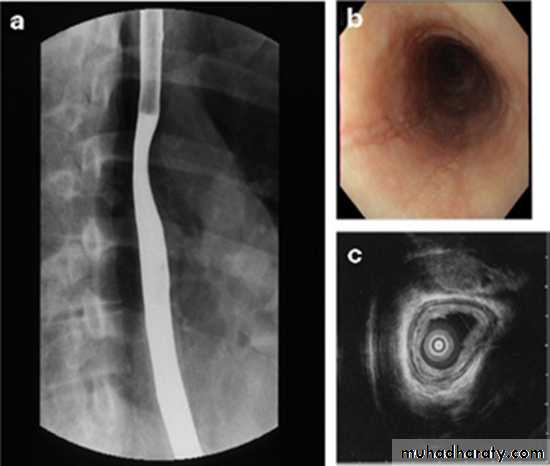

Barium Swallow:1. Conventional2. Double contrast (DC)3. Flouroscopy + spot filmsTechnique:

The Normal Anatomy: *Long tubular structure * Length 25-30 cm* Start at level of C5 ( Crico-pharengeal)* End – Cardiac sphincter* Three portions Cervical Thoracic Abdominal* Normal Mucosal pattern (DC) thin regular longitudinal Parallel Numbers of lines ( 4-5 )

Areas of normal Narrowings:- body of the cervical vertebra - AA- LT atrium- diaphragmatic hiatus

Esophagus mucosa: normal thin, parallel, uniform mucosal folds 3-4 in no.in double contrast examination